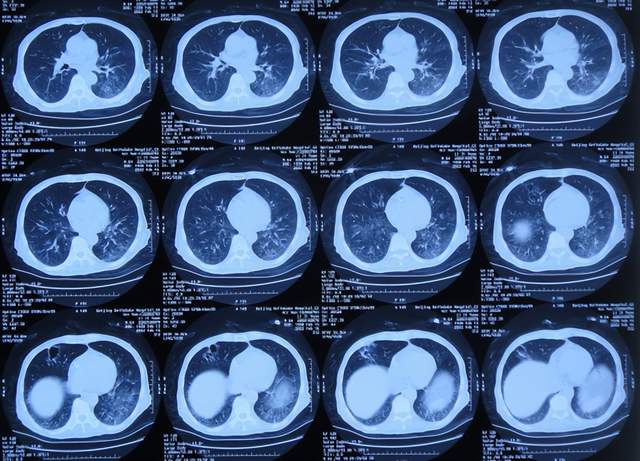

患者于2021年9月2日突发昏迷,急送至当地的山东省滨州市惠民县某医院,查头颅CT示脑出血破入脑室(图-1),急诊行双侧脑室外引流术;脑出血后血压偏低,给予输注入人血白蛋白。

图-1:2021年9月2日头颅CT

术后次日即2021年9月3日,患者意识转清醒,能简单言语,肢体可以遵嘱抬起;查头颅CT示双侧脑室引流术后,脑室积血(图-2)。

图-2:2021年9月3日头颅CT

双侧脑室外引流术后3天即2021年9月5日,查头颅CT示脑室内积血减少(图-3)。

图-3:2021年9月5日头颅CT

双侧脑室外引流术后6天即2021年9月8日,再次查头颅CT示仍有少量积血(图-4);给予常规拔除了双侧脑室外引流管,同时进行了腰大池引流术。

图-4:2021年9月8日头颅CT

腰大池引流术后4天即2021年9月12日,查头颅CT示脑室内积血基本消失(图-5)。

图-5:2021年9月12日头颅CT

腰大池引流术后8天即2021年9月20日,给予拔除腰大池引流管,之后给予保守治疗。

拔除腰大池引流管后3天即2021年9月23日,查头颅CT示(图-6)后继续给予保守治疗。

图-6:2021年9月23日头颅CT

腰大池引流管拔除后13天即2021年10月3日,患者恢复至可以搀扶下行走约20米,能简单言语,查头颅CT较2021年9月23日认为没有明显变化(图-7)。

图-7:2021年10月3日头颅CT

但继续保留治疗20余天的时间内,患者逐渐出现意识变差,走路变差,至2021年11月3日(腰大池引流管拔除后31天),病情变重致不能走路,不能言语,查头颅CT(图-8)后考虑脑积水,给予腰椎穿刺治疗。

图-8:2021年11月3日头颅CT

但腰椎穿刺治疗7天病情无明显改善,于2021年11月10日(住院治疗2月余)出院回家休养,出院时头颅CT示仍有脑积水(图-9);出院时:意识差,不能走路,不能言语。

图-9:2021年11月10日头颅CT

出院1个半月后,因患者病情无改善,家属想做脑室腹腔分流术,于2021年12月22日前往上级的山东省滨州市某三甲医院就诊,查头颅CT示脑积水(图-10);但腰椎穿刺检查示颅内压低;胸部CT有肺部脓肿(片子丢失),暂时给予抗感染治疗。

图-10:2021年12月22日头颅CT

给予抗感染治疗个月后即2022年1月17日,肺部脓肿明显变小(片子丢失),查头颅CT仍脑积水(图-11),未给予脑室腹腔分流术,建议暂时回家休养,但患者意识仍不好,不能走路,不能说话,体型变消瘦。

图-11:2022年1月17日头颅CT